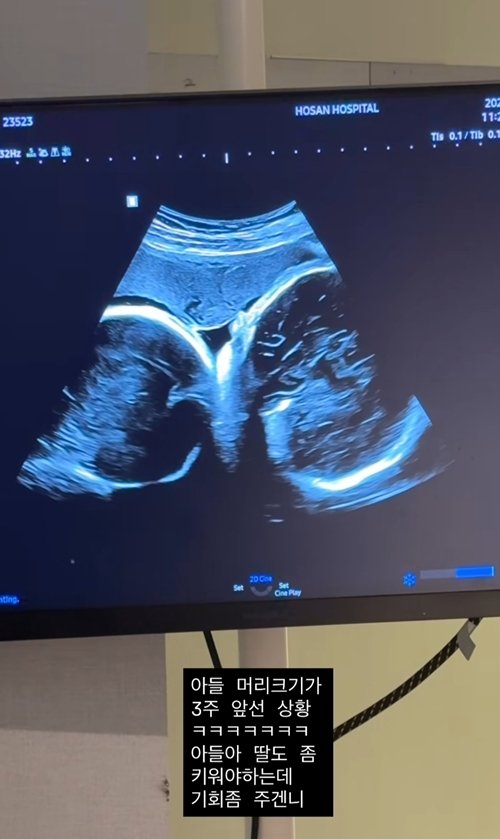

| 2025년 8월 25일 | **쌍둥이 초음파 영상 공개**. 아들 머리 크기가 딸보다 3주 앞선다고 언급하며 유쾌한 심경 토로. | 개인 SNS |

**지소연** 씨는 과거 **난임**과 유산이라는 아픔을 겪었음을 솔직하게 고백하며 많은 이들의 공감을 얻었습니다. 그런 그녀가 2023년 첫딸을 얻은 데 이어, 이번에는 **남매 쌍둥이 임신**이라는 두 배의 기쁨을 맞이하게 된 것이죠. 이번 **초음파 공개**에서 아들의 머리 크기가 딸보다 3주 앞서고 있다는 사실을 유쾌하게 전하며 딸의 성장을 걱정하는 모습은, 아이들을 향한 엄마의 깊은 사랑과 더불어 그녀가 겪어온 쉽지 않은 과정을 짐작게 합니다. 이는 수많은 **난임** 부부들에게 희망과 위로를 전하는 메시지가 되고 있습니다.

A. **지소연** 씨는 현재 **남매 쌍둥이**를 임신 중입니다. 2023년 첫딸 출산 이후 둘째 임신 소식이며, 건강하게 출산을 준비하고 있습니다. **초음파 공개**를 통해 아들 머리가 딸보다 3주 크다는 유쾌한 소식도 전했죠.